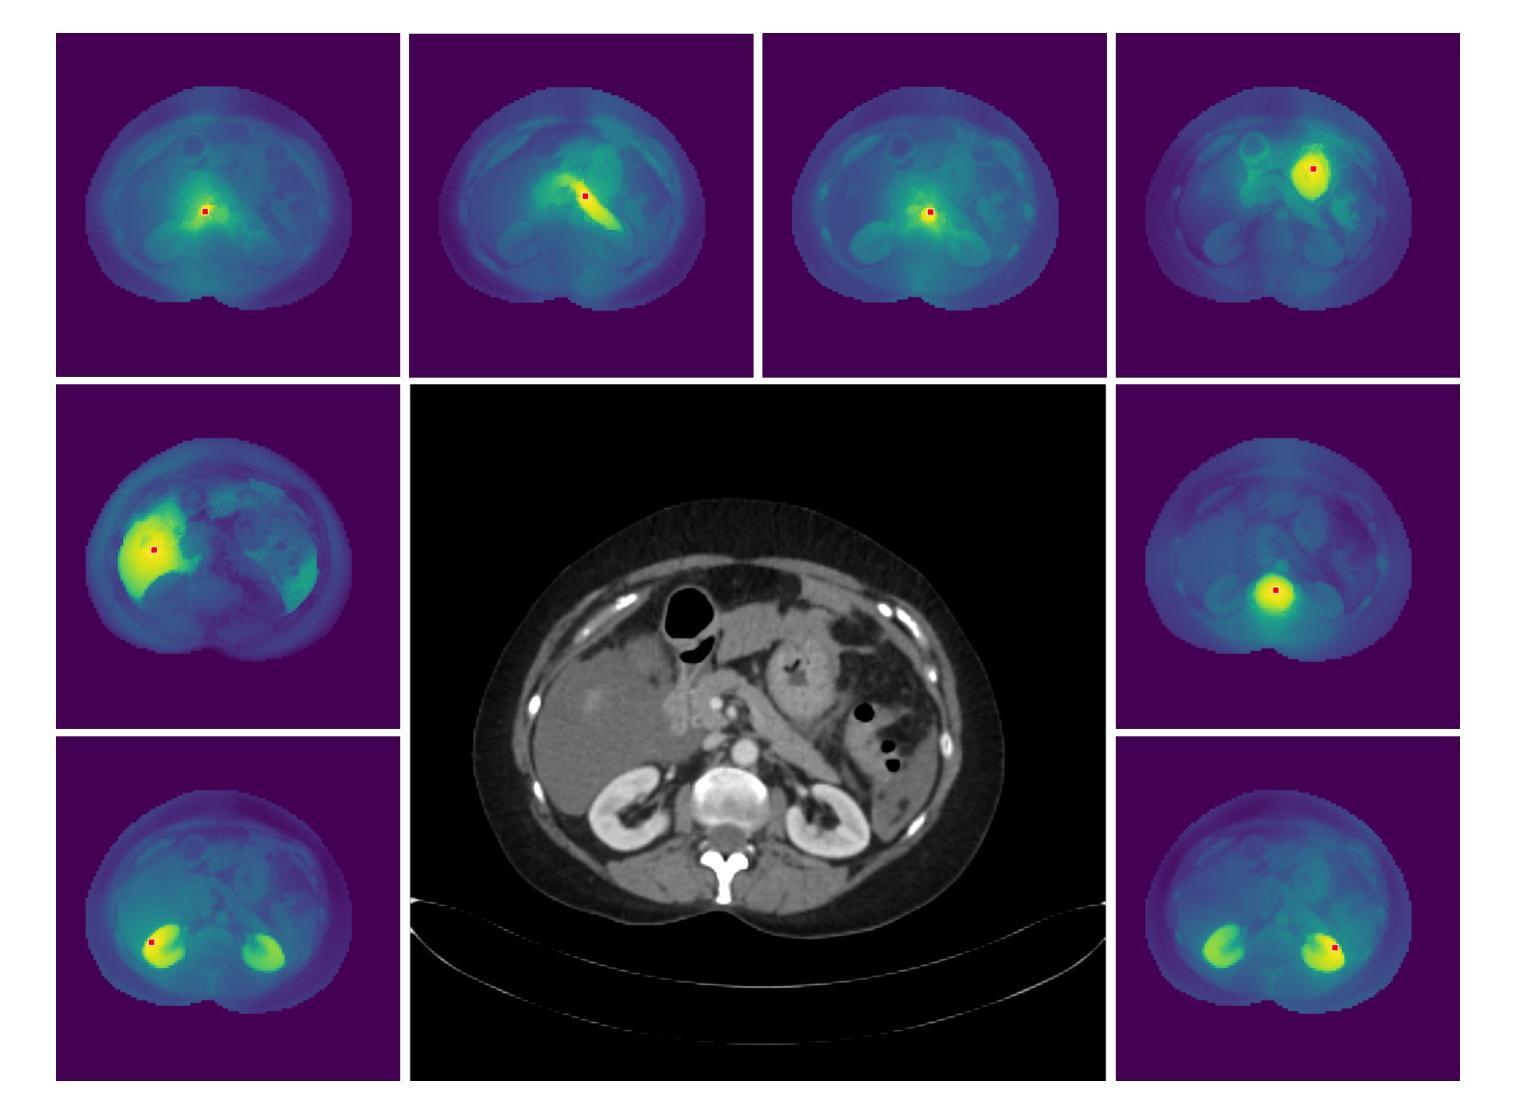

Oral and maxillofacial radiology plays a vital role in dental healthcare, but radiographic image interpretation is limited by a shortage of trained professionals. While AI approaches have shown promise, existing dental AI systems are restricted by their single-modality focus, task-specific design, and reliance on costly labeled data, hindering their generalization across diverse clinical scenarios. To address these challenges, we introduce DentVFM, the first family of vision foundation models (VFMs) designed for dentistry. DentVFM generates task-agnostic visual representations for a wide range of dental applications and uses self-supervised learning on DentVista, a large curated dental imaging dataset with approximately 1.6 million multi-modal radiographic images from various medical centers. DentVFM includes 2D and 3D variants based on the Vision Transformer (ViT) architecture. To address gaps in dental intelligence assessment and benchmarks, we introduce DentBench, a comprehensive benchmark covering eight dental subspecialties, more diseases, imaging modalities, and a wide geographical distribution. DentVFM shows impressive generalist intelligence, demonstrating robust generalization to diverse dental tasks, such as disease diagnosis, treatment analysis, biomarker identification, and anatomical landmark detection and segmentation. Experimental results indicate DentVFM significantly outperforms supervised, self-supervised, and weakly supervised baselines, offering superior generalization, label efficiency, and scalability. Additionally, DentVFM enables cross-modality diagnostics, providing more reliable results than experienced dentists in situations where conventional imaging is unavailable. DentVFM sets a new paradigm for dental AI, offering a scalable, adaptable, and label-efficient model to improve intelligent dental healthcare and address critical gaps in global oral healthcare.

口腔颌面放射学在牙科健康护理中扮演着至关重要的角色,但由于训练有素的专业人员短缺,放射学图像解读受到限制。虽然人工智能方法已经展现出潜力,但现有的牙科人工智能系统受到其单一模态关注点、特定任务设计和依赖昂贵标注数据的限制,阻碍了它们在各种临床场景中的泛化能力。为了应对这些挑战,我们推出了DentVFM,这是为牙科设计的第一代视觉基础模型(VFMs)。DentVFM为各种牙科应用生成任务通用的视觉表示,并使用自我监督学习在DentVista(一个大型精选牙科成像数据集)上进行训练,该数据集包含来自不同医疗中心的约160万多种模态的放射图像。DentVFM包括基于视觉转换器(ViT)架构的2D和3D变体。为了解决牙科智能评估和基准测试的空白,我们推出了DentBench,这是一个全面的基准测试,涵盖八个牙科专科、更多疾病、成像方式和广泛的地理分布。DentVFM展现了令人印象深刻的通用智能,表现出对各种牙科任务的稳健泛化能力,如疾病诊断、治疗分析、生物标志物识别以及解剖地标检测和分割。实验结果表明,DentVFM显著优于监督学习、自我监督学习和弱监督学习的基线,具有出色的泛化能力、标签效率和可扩展性。此外,DentVFM能够实现跨模态诊断,在常规成像无法获取的情况下提供更可靠的结果,其诊断结果甚至比经验丰富的牙医还要可靠。DentVFM为牙科人工智能设定了新的范式,提供了一个可扩展、可适应和标签效率高的模型,以改善智能牙科健康护理,并解决全球口腔健康护理中的关键差距。